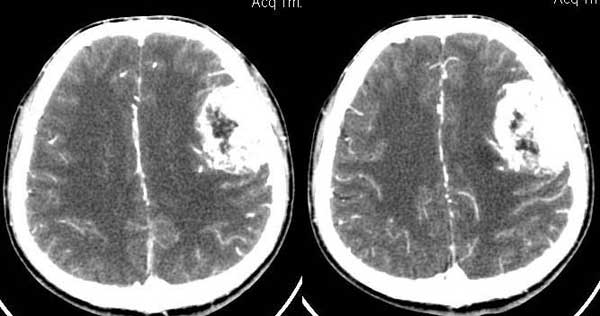

左颞部稍低密度d形肿块影阴,密度不均,内有不规则囊变区,局部脑白质受压塌陷,肿块周围少许水肿带,中线轻度右移位,增强扫描明显强化,局部颅板有轻微侵蚀,如此大的肿块中线结构移位不明显说明肿块位于脑外,如此强化的脑外肿瘤只有一个------脑膜瘤

本例我首先考虑脑膜瘤,但其具有形态不规则、密度不均匀、有明显的坏死液化、没有完整和明显的包膜、且呈明显不均匀性强化等诸多恶性特点,应该首先考虑恶性脑膜瘤(但颅骨只有轻微受压而没有明显的受浸润破坏现象也不太支持)。

皮质塌陷,增强比较明显,有一定的占位效应,脑内轻度水肿,脑外病变可肯定,考虑脑膜瘤,颅骨内板见局限侵袭改变,警惕恶变

左侧颞顶叶见d形肿块灶,密度不均,其内可见低密度影,局部脑白质所压移位,病灶明显强化。支持脑膜瘤